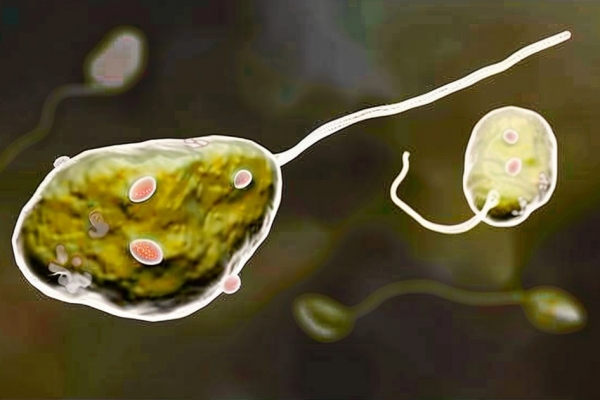

食脑虫会传染吗

食脑虫会传染吗

阿米巴原虫是什么

阿米巴原虫是什么

阿米巴原虫怎么治疗

阿米巴原虫怎么治疗